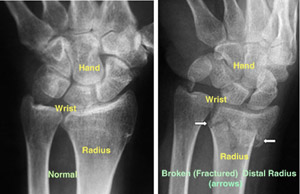

To confirm the diagnosis, the doctor will order x-rays of the wrist. X-rays are the most common and widely available diagnostic imaging technique. X-rays can show if the bone is broken and whether there is displacement (a gap between broken bones). They can also show how many pieces of broken bone there are.

(Left) An x-ray of a normal wrist. (Right) The white arrows point to a distal radius fracture.